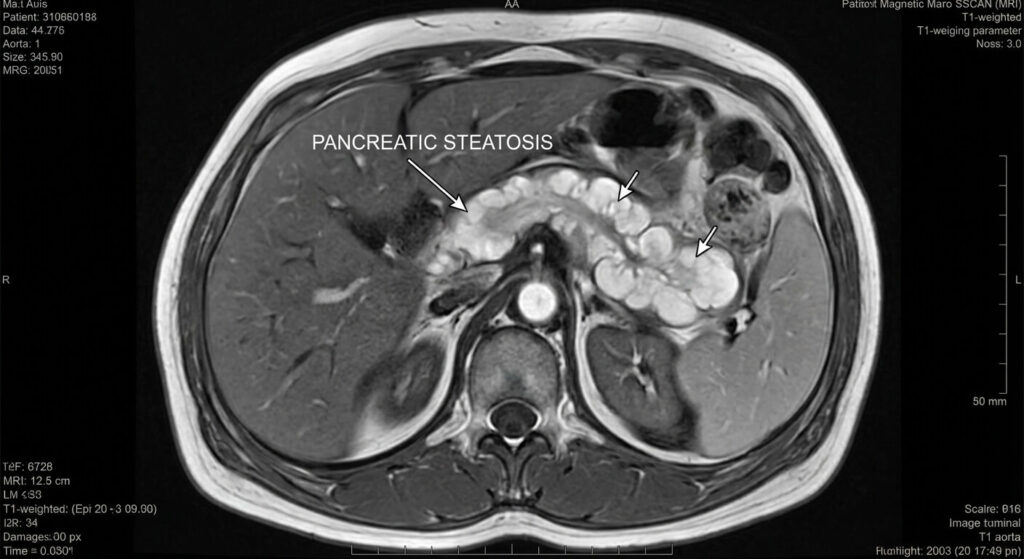

Non, la biologie est trompeuse à ce stade. Vos dosages sanguins classiques (lipase, amylase, glycémie) peuvent être strictement dans les normes de laboratoire, alors que votre pancréas est déjà gorgé de graisse à 30 %. Le pancréas possède une grande « réserve fonctionnelle » et compense la destruction de ses cellules pendant très longtemps. C’est pourquoi seule l’imagerie médicale (échographie, scanner ou IRM abdominale) permet de poser le diagnostic d’involution graisseuse de manière visuelle et certaine.